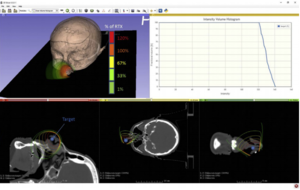

Publication: Brachytherapy. 2016 Jul-Aug;15(4):514-23. PMID: 27180127 Authors: Siavashpour Z, Aghamiri MR, Jaberi R, Dehghan-Manshadi HR, Sedaghat M, Kirisits C. Institution: Department of Medical Radiation Engineering, Shahid Beheshti University, Tehran, Iran. Background/Purpose: To demonstrate the utility of 3D Slicer for easy treatment verification by comparing dose-volume histograms (DVHs) calculated on pretreatment and post-treatment images. Methods and Materials: Thirty cervical cancer patients were CT scanned twice: first for treatment planning and a second time after the dose delivery. The initial plan was manually duplicated on the post-treatment image set in Flexiplan treatment planning system, and DVH parameters were calculated. Pretreatment and post-treatment images, organ structures, and plan data were exported from the treatment planning system to 3D Slicer to validate DVH parameter calculation with 3D Slicer. The gamma analysis was used to compare Flexiplan and 3D Slicer DVHs. Post-treatment images were rigidly fused on the initial CT to automatically transfer the data of the pretreatment plan onto the post-treatment images. DVH parameters were calculated in 3D Slicer for both image sets, and their relative variations were compared. Results: In calculating DVH parameter variations, no significant differences were observed between Flexiplan and 3D Slicer. Where the registration accuracy was better than 0.03, they returned similar results for D2 cm3 of bladder, rectum, and sigmoid. Mean and standard deviation of DVH parameters were calculated on pretreatment and posttreatment images for several organs; both the manually duplicated plan and the automatically registered plan in SlicerRT returned comparable relative variations of these parameters. For 88% of the organs, more than 95% of the DVH dose bins passed the gamma analysis. Conclusions: We tested an automated DVH assessment method with an imaging freeware, 3D Slicer, for use in image-guided adaptive brachytherapy. SlicerRT is a viable verification tool to report and detect DVH variations between different contoured images series. |

- 1.20 Evaluating the Utility of "3D Slicer" as a Fast and Independent Tool to Assess Intrafractional Organ Dose Variations in Gynecological Brachytherapy